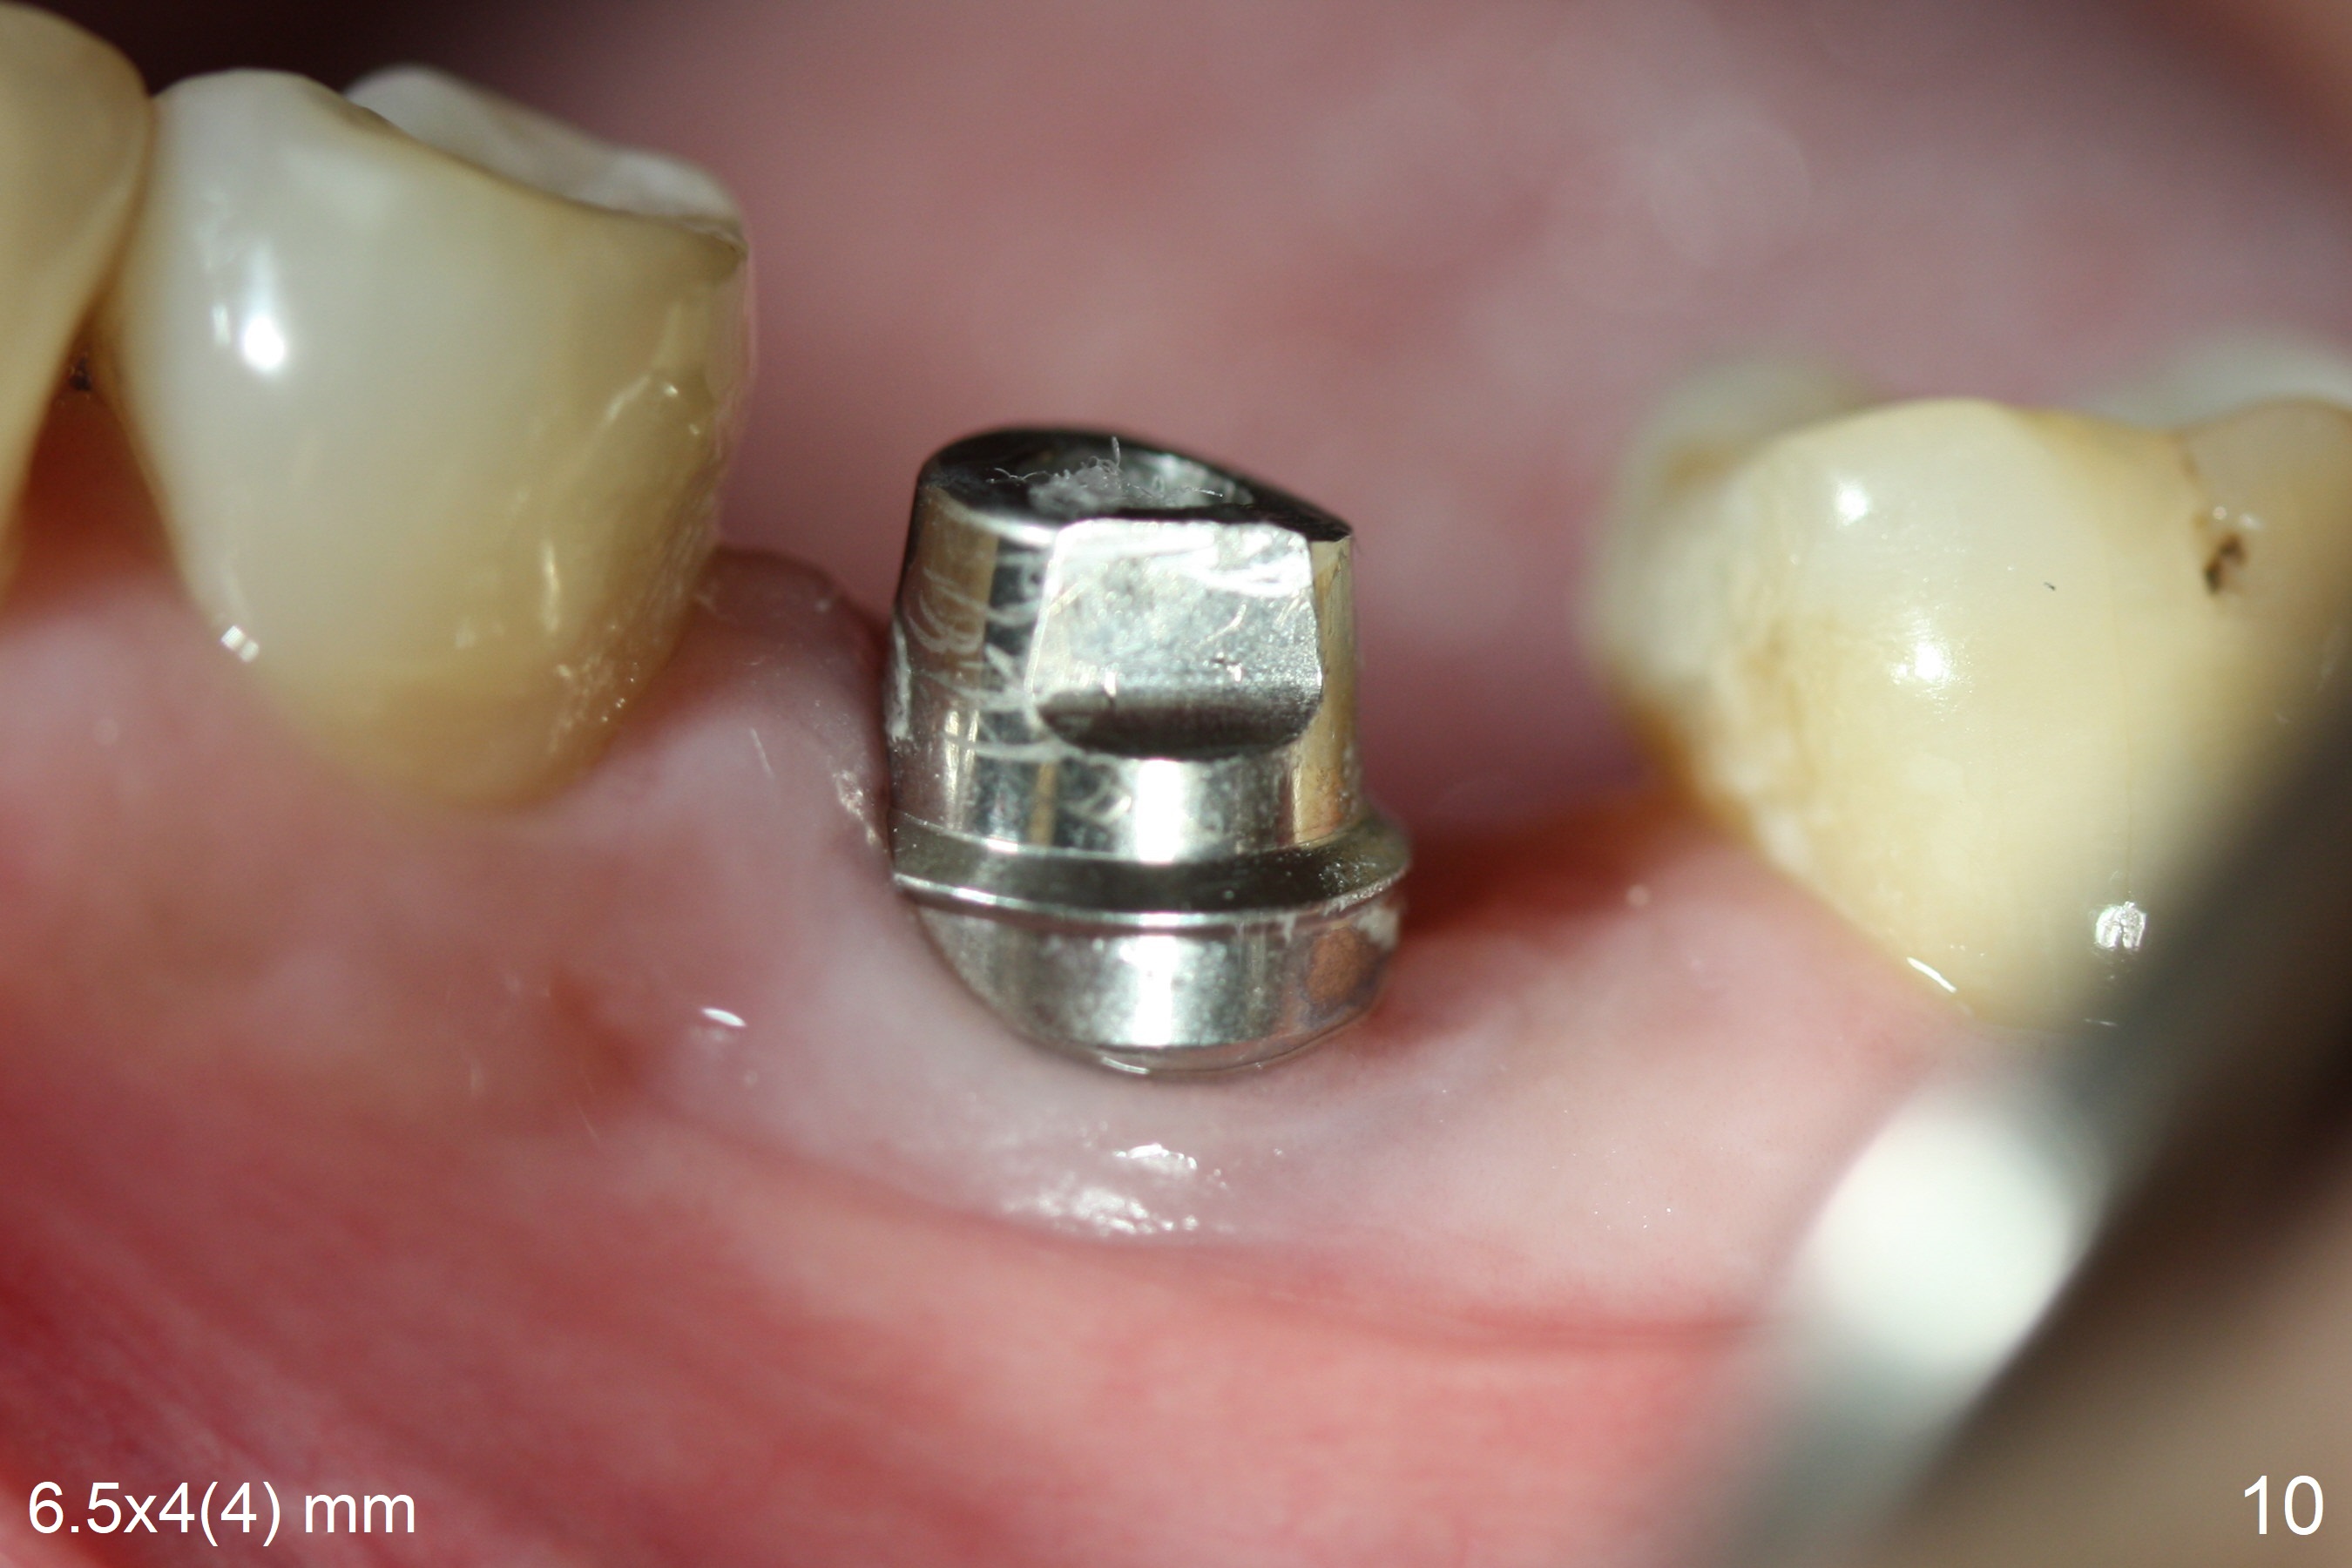

When the patient returns 9 months later, there is severe buccal gingival recession and abscess at #19 (Fig.1 *) with large mesial periradicular radiolucency (Fig.2 *).  The septum is thin and the buccal crest is low after extraction (Fig.3 * (mesial root vertical fracture)).  Osteotomy is initiated in the mesial socket immediately against the septum (Fig.4.5) with ~ 5 mm in the native bone.  Due to severe buccal plate resorption, a shorter implant is placed (Fig.6; 5x15 mm in stead of 18 mm).  There is at least 2 mm gap buccally for Vanilla Graft, which is also placed next to the implant and the neighboring root (Fig.7 *).  There is clearance from the Inferior Alveolar Canal (Fig.8 red dashed line).  Both the mesial and distal sockets heal 5.5 months postop (Fig.9), although the apical portion of the distal socket was not filled with allograft (Fig.7).  The implant was placed mesial.  The straight abutment (6.5x4(4) mm) (Fig.10) is changed to an angled one (5.5 x15 degrees 3 mm cuff (Fig.11)) before impression.  The implant is also placed buccally.  Therefore the implant position is far more important than its length.  The abutment is retightened 2.5 months post cementation, which is related to mesiobuccal placement of the implant (Fig.12).  An ideal trajectory is determined by drawing 2 horizontal lines (at crestal and apical levels: red lines in Fig.13), finding a central point of each line (vertical short line) and joining these 2 central points (Fig.14 pink line).  In fact the ideal osteotomy should have been established distal to the septum in this case.  Guided surgery may alleviate the issue.  The crown is not loose, but the patient feels that the implant tooth cannot sustain mastication.  In fact the screw is removed with hand driver (not wrench).  The abutment hex is rounded and worn.  A new 5.5x4(4) mm abutment is placed (without knowledge of previous use of an angled abutment) with mesial reduction to reduce undercut and buccodistal margin lowered to reduce gingival embrasure. It is that the straight abutment could decrease the chance of screw loosening.  Otherwise the implant has to be removed for better trajectory.